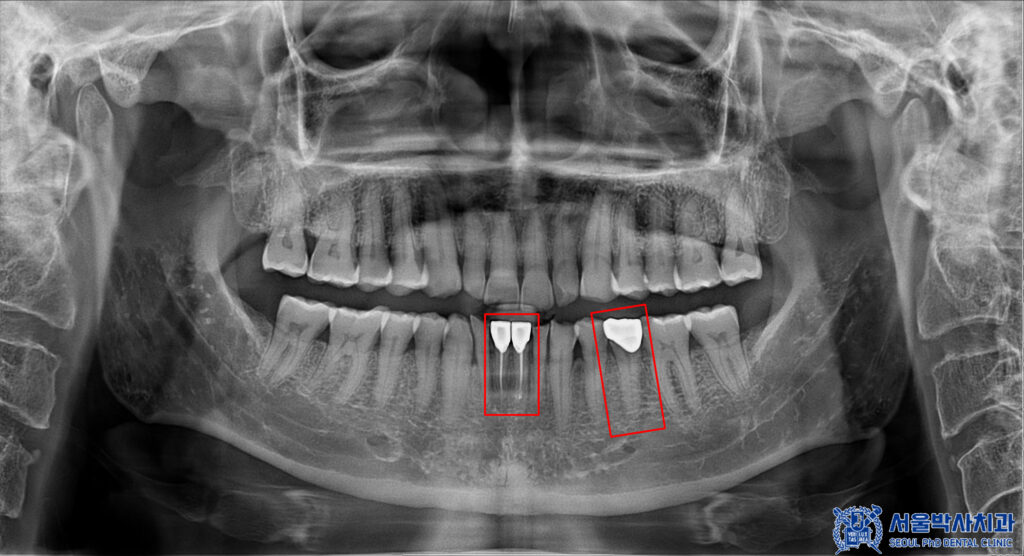

또한 파노라마를 확인해 보니,

왼쪽 아래 앞니는 과거에

신경치료가 시행된 치아였으나

치아 뿌리 끝 부위에 염증 소견이

관찰되었습니다.

이에 따라 기존 치료 부위를

다시 정리하고 염증을 제거하기 위해

재신경치료를 진행하기로

결정하였습니다.

더불어 해당 치아와 맞닿아 있는

옆 앞니 역시 뿌리 끝 염증이 확인되어,

염증의 확산과 추가적인 문제를 예방하기 위해

함께 신경치료를 시행하기로 하였습니다.